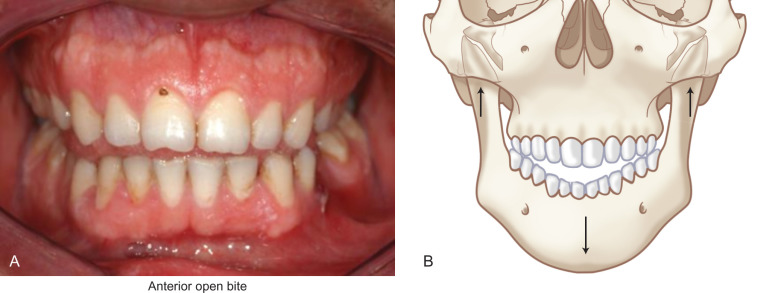

Because the lateral pterygoid muscle inserts mostly onto the pterygoid fovea of the condyle, when a fracture occurs below this level, contraction of the muscle causes the condylar fragment to be displaced anteromedially. For the same reason, condylar fractures are associated with impaired translational movement of the condyle along the articular eminence because the lateral pterygoid muscle is no longer connected to the distal portion of the mandible ( Fig. 1.15.1 ). Although rotation can occur, lack of translation produces a characteristic deviation of the chin on opening toward the side of a unilateral condylar fracture ( Fig. 1.15.2 ). Displacement of the condylar process produces a loss in the anatomic height of the ramus, which allows premature contact of the ipsilateral most distal tooth ( Fig. 1.15.3 ). The point of contact acts as a fulcrum and produces a characteristic open-bite on the side opposite of a unilateral fracture ( Fig. 1.15.3 ). Bilaterally displaced fractures of the condylar processes produce a symmetric anterior open-bite ( Fig. 1.15.4 ).